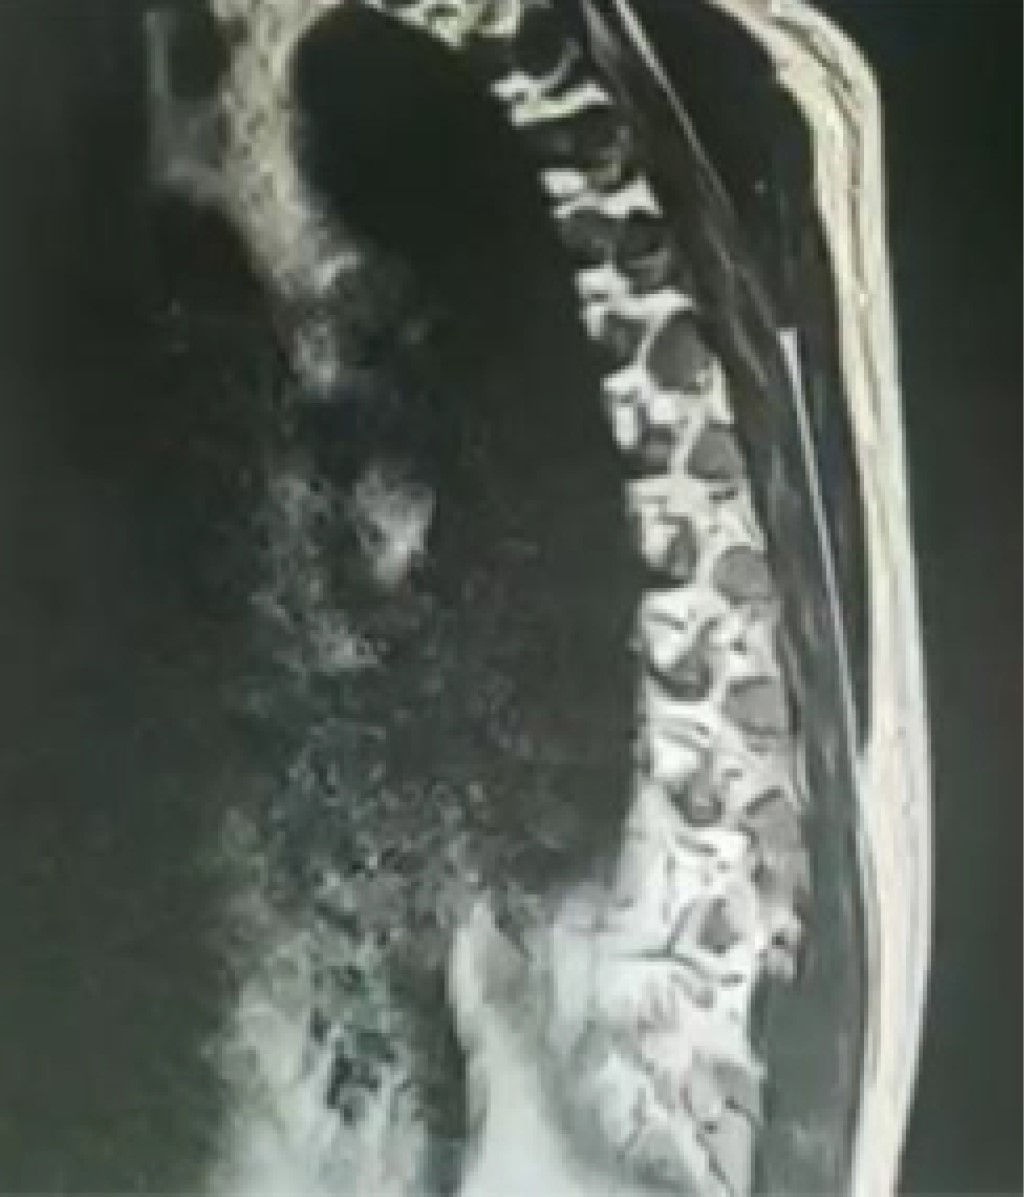

Figure 2

There are around 1.7 billion people worldwide with latent Mycobacterium tuberculosis infection (LTBI). All kidney transplant recipients and their donors should be screened for LTBI and active tuberculosis disease prior to transplant. The incidence in post-transplant patients is higher than the general population. There is no gold standard test to accurately diagnose LTBI. The WHO recommends three tests for the detection of LTBI: the tuberculin skin test (TST) and two interferon gamma release assays (IGRA), namely QuantiFERON1-TB (QFT) Gold In-Tube and T-SPOT1 T ( WHO, 2018b). The TST can be unreliable in patients with advanced chronic kidney disease and in those taking immunosuppressive agents. Tuberculosis in the renal graft is a rare pathology, clinically it lacks the classic picture of constitutive syndrome, most of the time the patient presents a negative tuberculin test and negative results in cultures. This case presented in a 30-year-old male with hematuria, sterile pyuria, persistent low back pain, seven years after kidney transplantation, donor and recipient with no history of contacts with tuberculosis and with negative PPD tests. The main causes of hematuria were addressed, ruling out viral, urological and oncological causes. A simple CT scan documented extrapulmonary tuberculosis (spinal column) and due to renal function deterioration, Gene Xpert was performed on urine and a renal biopsy was decided due to proteinuria in the subnephrotic range and active sediment, concluding a diagnosis of tuberculosis of the renal graft, causing its loss. Renal graft tuberculosis is a potential cause of graft dysfunction and loss, requiring a high index of suspicion for diagnosis. Timely detection and early institution of therapy may help renal allograft survival. The treatment represents a challenge for the clinician due to the interaction of antifungal drugs with immunosuppressants of the transplanted patient.